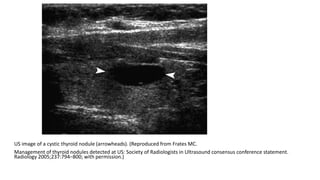

US image of a cystic thyroid nodule (arrowheads). (Reproduced from Frates MC.

Management of thyroid nodules detected at US: Society of Radiologists in Ultrasound consensus conference statement.

Radiology 2005;237:794–800; with permission.)